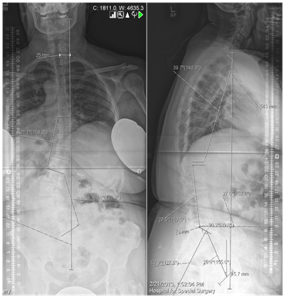

- Psychological assessment of elderly is very valuable before major surgery (Figure 5,6).

Figure 5 Whole spine x ray films in coronal and sagittal planes.

Figure 6 Spino-Pelvic alignment.